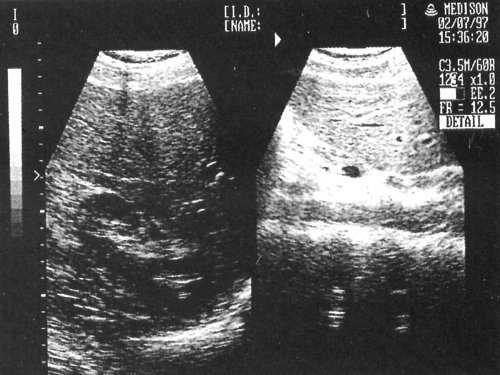

В норме большая часть печени располагается справа от позвоночника, а меньшая - слева от него и доходит до левой парастернальной линии. Контуры печени ровные, она имеет четкое очертание, капсула хорошо просматривается в виде гиперэхогенной структуры, окружающей ее паренхиму (за исключением участков, прилежащих к диафрагме, где капсула не дифференцируется от последней). В норме нижний край печени не выступает из-под реберной дуги. Общепринятыми являются измерение косого вертикального размера правой доли (не превышает 13-15 см) и толщины левой доли (до 5 см). Структура неизмененной печени представлена мелкозернистым изображением, состоящим из множества мелких точечных и линейных структур, равномерно расположенных по всей площади полученного среза. По эхогенности паренхима нормальной печени сопоставима или несколько выше эхогенности коркового вещества почки (при отсутствии ее патологии). Эхография позволяет дифференцировать различные трубчатые структуры, находящиеся в печени.

Рис. 1. Эхографическая картина нормальных левой и правой долей печени.